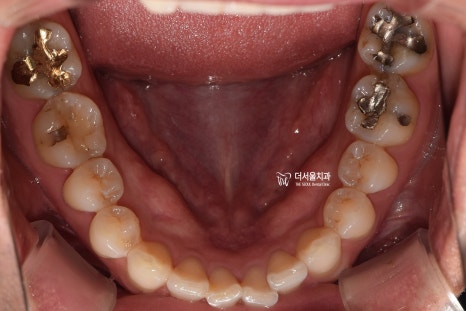

『1. 치아 상태 확인』

정면, 측면, 교합면 등 여러가지 방향에서

환자가 가지고 있는 치열의 상태를 먼저 확인합니다.

삐뚤빼뚤한 곳은 있는지, 또는 거꾸로 물리는 곳은

없는지, 나아가 충치 및 염증을 가지거나

치아 이동에 방해가 될 수 있는 사랑니를

가지고 있는지, 결손치나 있는지 등을

면밀하게 살펴보게 됩니다.